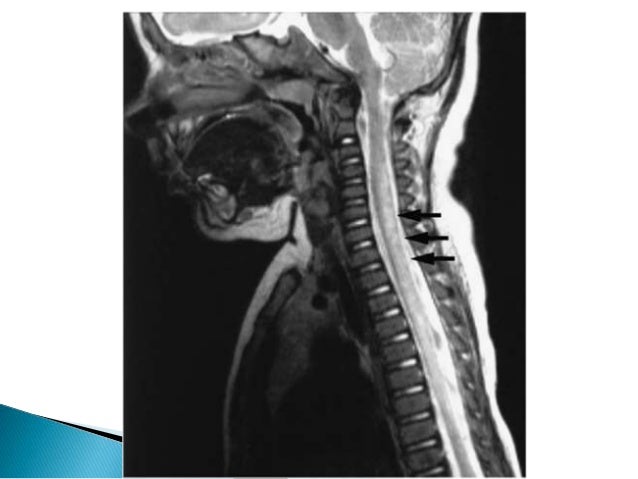

34. 34.  Lesions are centrally located and necrotic leading to more symmetric symptoms and signs and greater disability  NMO is relatively more common in Asian and African individuals, Female preponderance with mean age of 40 yrs.  Autoimmune conditions including SLE, SjoGren syndrome, and thyroid autoimmune disorders may coexist

36. 36.  Radiological characteristics include a central longitudinal and extensive cervicodorsal lesion (three or more spinal segments) with spinal expansion, of low signal in T1 sequences and high signal in T2 sequences and patchy enhancement.  It has been demonstrated that 60% of patients may have periventricular lesions (areas of high aquaporin 4 concentration).  In this case, NMO is not associated with cerebral white matter lesions, and the spinal lesions are confluent and extend to multiple segments (which is infrequent in MS);  Cranial nerve and cerebellar involvement is common in MS and is not present in NMO.

37. 37.  NMO-IgG -against Aquaporin 4(water channel protein)recently identified serum antibody highly specific (>90%) and sensitive (>70%) for NMO.  Typically oligoclonal bands are absent(unlike in MS)

9. 9. INHERITED- HSP, Inherited metabolic disorders METABOLIC- Vit. B12,Copper,folate and Vit. E deficiency. AIDS Associated. TOXIC –Cassava, Lathyrism, Fluorosis, SMON, Nitrous Oxide VASCULAR – Ant. Spinal artery thrombosis, AVM, Dural AV fistula